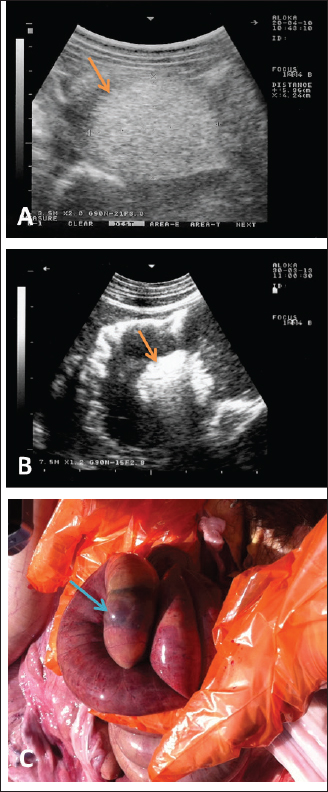

Sonographic and postmortem findings are summarized in Table 2. In cases of camels presented with a history of pica and with decreased or total absence of feces, the obstructing foreign body was imaged in 10 of the 25 camels (40%) occluding completely or partially the intestines that may be confirmed at abdominal surgery (Figs. 2, 3, and 6). Foreign bodies within the rumen could not be visualized with ultrasound owing to the gas content. In cases where the rumen is impacted by sand, small pin-points revealing acoustic enhancement were imaged in 5 (20%) of the camels. An example of these cases is shown in Figure 7. Foreign bodies were removed from the rumen or intestines at exploratory rumenotomy and laparotomy, which included plastics, cloths, sand, mud, robes, wool balls, glasses, or even metallic objects that were blunt or sharp (Figs. 8 and 9).

Fig. 6. Ultrasonographic findings in camels with depraved appetite. In image (A), a wool ball (5.4 × 4.2 cm) was detected obstructed the small intestines in an adult male camel (arrow). Image (B) shows a foreign body detected within the small intestines in a 5-day female camel calf (arrow). Images were taken from the right lower abdomen using 3.5 and 7.5 MHz sector transducers, respectively. Image (C) shows the obstructing wool ball detected at necropsy of the camel shown in Fig. 6A.

During the past 13 years, our research group has focused on the effectiveness of diagnostic imaging techniques in dromedary camels either in the healthy or diseased conditions (El-Tookhy and Tharwat, 2012; Ali et al., 2018; Al-Sobayil et al., 2018; Tharwat et al., 2012a,b,c,d; Tharwat, 2013a; Tharwat et al., 2013; Tharwat and Al-Sobayil, 2016a; Tharwat et al., 2018a; Tharwat, 2019; Tharwat, 2020a,b,c; Tharwat, 2021a,b; Tharwat and Al-Hawas, 2021; Tharwat and El-Tookhy, 2021; Tharwat et al., 2021; Tharwat and Al-Hawas, 2023; Tharwat et al., 2023; Tharwat,$ 2024; Tharwat and Al-Hawas, 2024). In these studies, the occluding foreign body was imaged obstructing the intestines either partially or completely. Because of the gaseous contents, the foreign bodies could not be localized within the rumen. However, in camels with rumen sand impaction, shining pin-points with acoustic enhancement are clearly visualized.